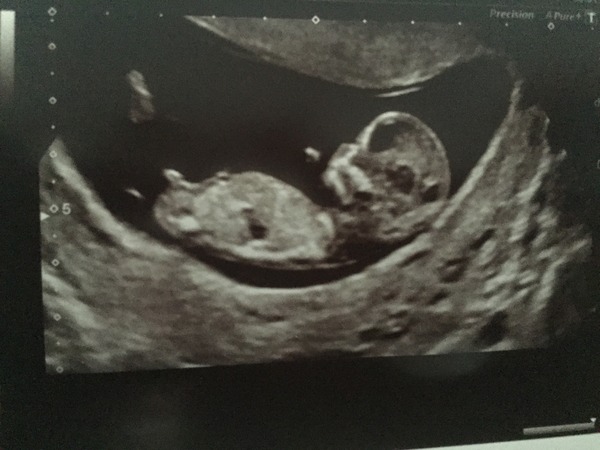

Would you guys mind working your nub and skull magic on my scan pic? I've only just had a chance to upload as been on hols.

Aww that's a super lovely scan pick Queazy really clear too. I would say boy from that pic. You got a super.good pock of the nub too, clear enough even I can see it! I think its a boy nuh, but the skull suggests boy.

I'm guessing its a boy too!